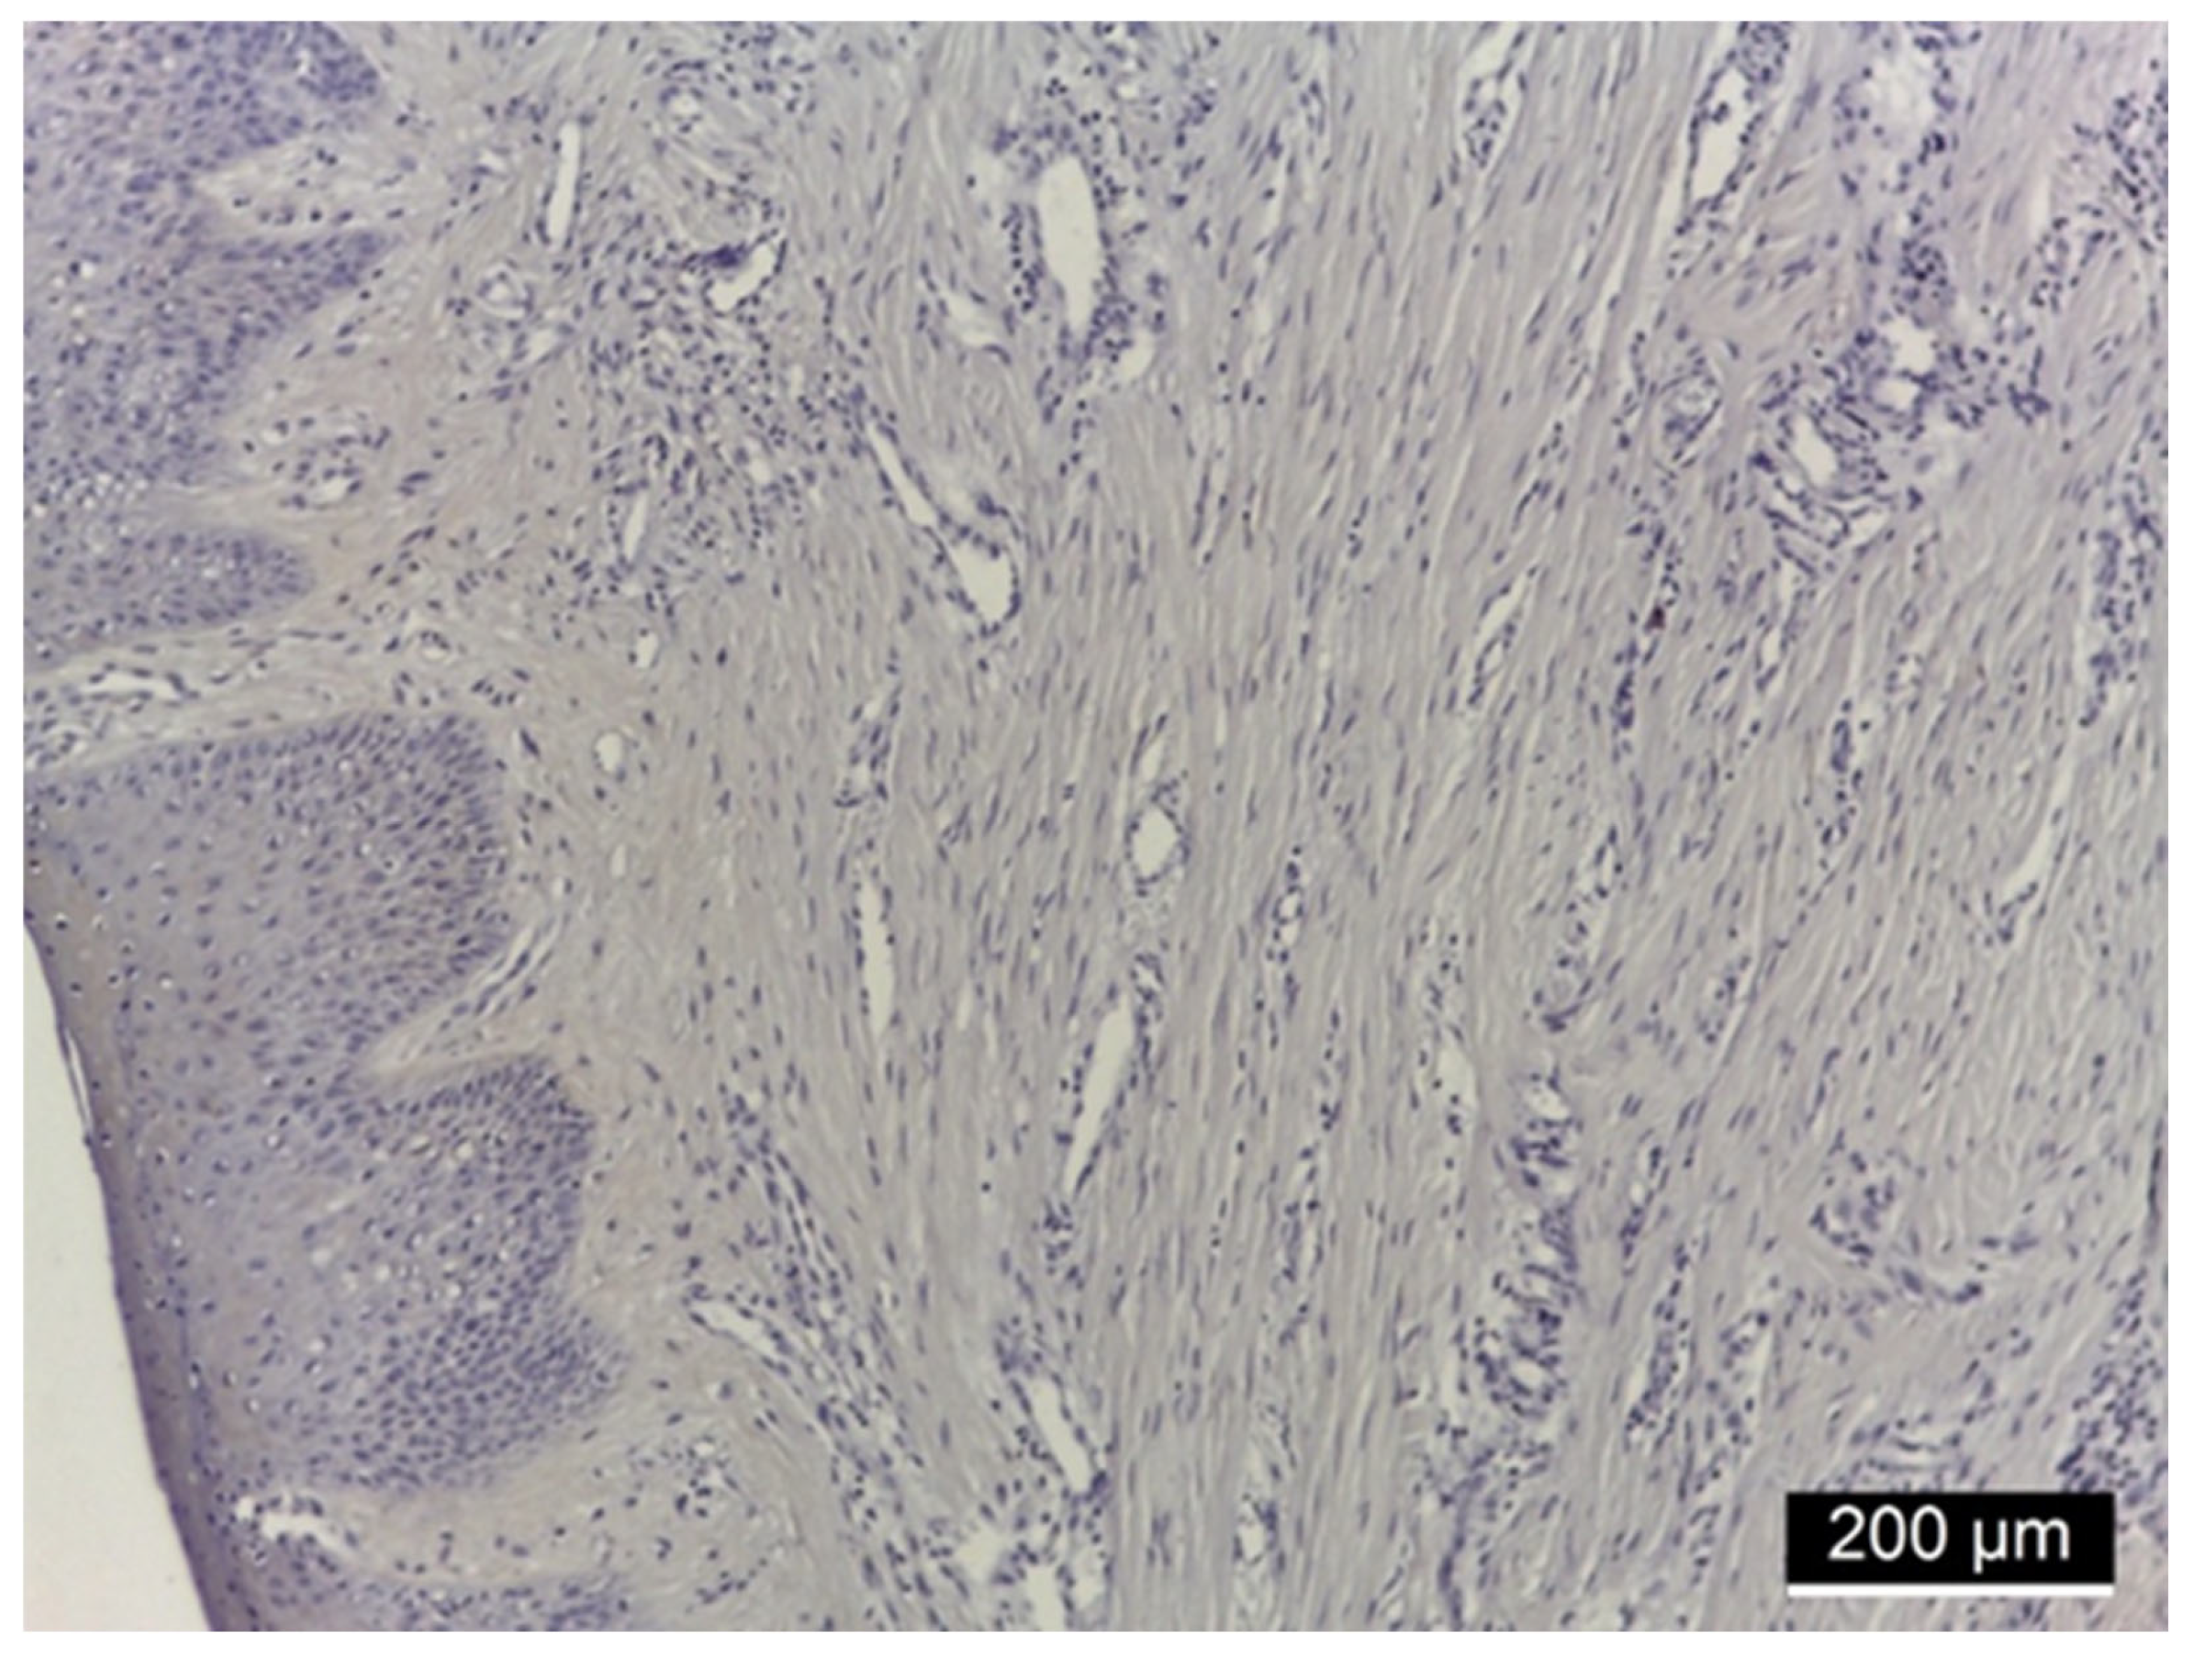

3.2. Ezrin Immunoreactivity

3.3. MMP-2 Immunoreactivity